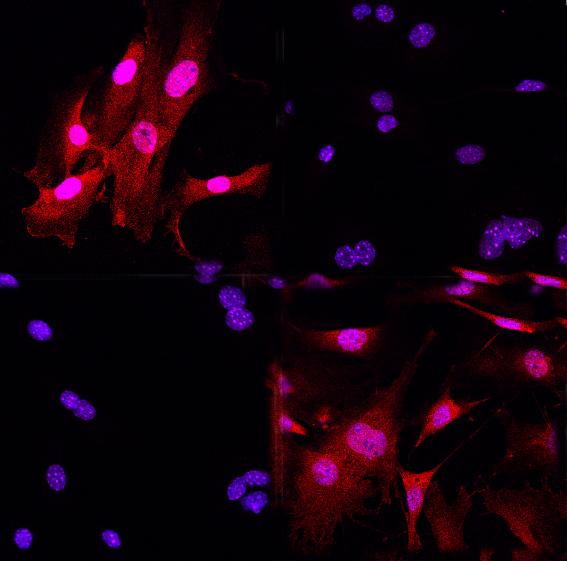

image: Immunofluorescent hue of the GR (glucocorticoid receptor, red) in mouse cells reacting to an inflammation signal - the cell nucleus is colored blue. You can see how - without steroids - the GR disperses in the cell's cytoplasm and how it is visible in the cell nucleus after the medication (dexamethasone) was administered (red and blue converge inside the round nucleus).

The work group around Henriette Uhlenhaut, Professor for Metabolic Programming at TUM School of Life Sciences in Freising-Weihenstephan and researcher in the field of Molecular Endocrinology at Helmholtz Zentrum München is working with so-called glucocorticoids. These are steroidal hormones such as cortisone, which are released by the adrenal glands every day before waking up or whenever a person is subjected to stress. These steroids are bound to their glucocorticoid receptor and control not only our body's immune reaction but also our sugar and fat metabolism.

As glucocorticoid receptors are so efficient at disabling immune reactions, synthetic steroid medication is among the most prescribed drugs overall and it has been for decades.